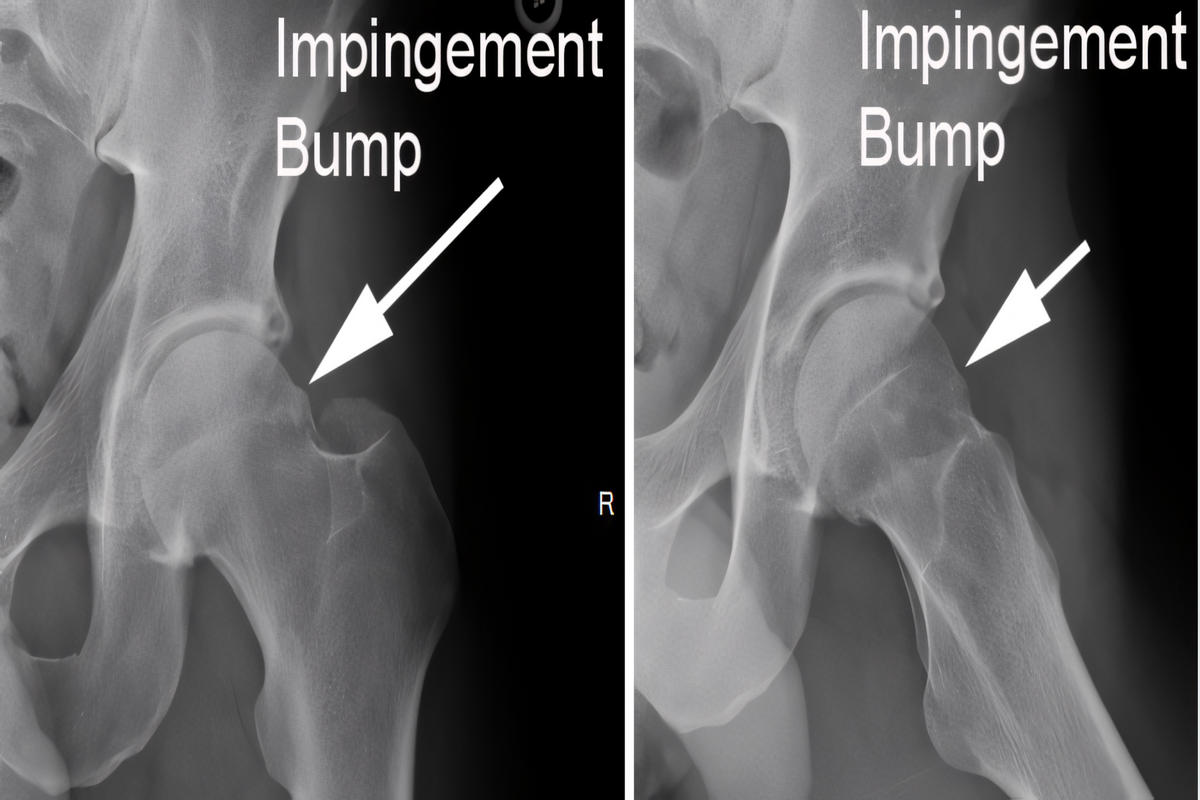

Απεικονιστικές εξετάσεις

Ακτινογραφίες λεκάνης και ισχίου για αξιολόγηση μορφολογίας